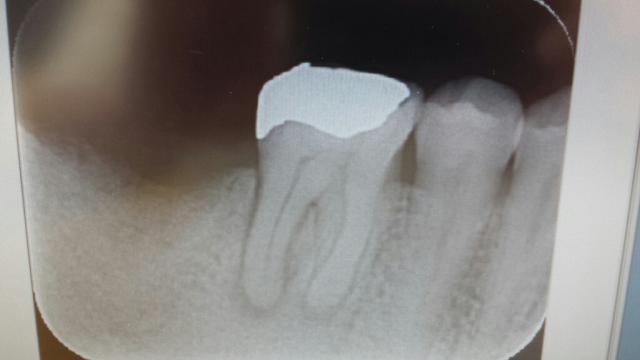

2015.07.19 [ 根管治療 ]

珍しい歯の内部吸収症例

歯の内部(歯髄)部分から吸収が起こり、最終的には歯が折れてしまう珍しい内部吸収について

頻度としては私の全患者のうち年間で1人いるかいないかというとても珍しい現象である。大抵のケースでは気づかないうちに徐々に進行して歯髄炎のような症状から発見されることが多いのが特徴である。強い咬合力がかかっている歯にストレスがかかると時として歯の内部吸収がおこるようである。

以前はメインテナンス時にはパノラマレントゲンで歯の虫歯や歯周病を確認していたのだが、2年前から14枚法のデンタル撮影のIPフィルムにに切り替えてからは発見が容易になっている。

今回のケースでは抜髄処置後に管内の内部吸収部にはMTAセメントを使用して歯の外部との交通部分を埋めて内部はファイバーコア+スーパーボンドで補強をして歯を抜かずに保存していく予定である。

左上の画像はわずか2年で内部吸収がおこった例

左下は内部吸収後にフラップ手術で管外からMTAセメント+CRで処置した例

今日は下顎大臼歯の4管の充填、1時間かけて形成して充填まで

画像は充填後と充填前